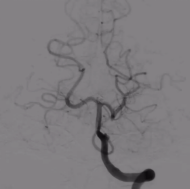

右侧大脑中动脉球囊扩张治疗前后对比图

颅内静脉窦狭窄支架治疗前后对比图、